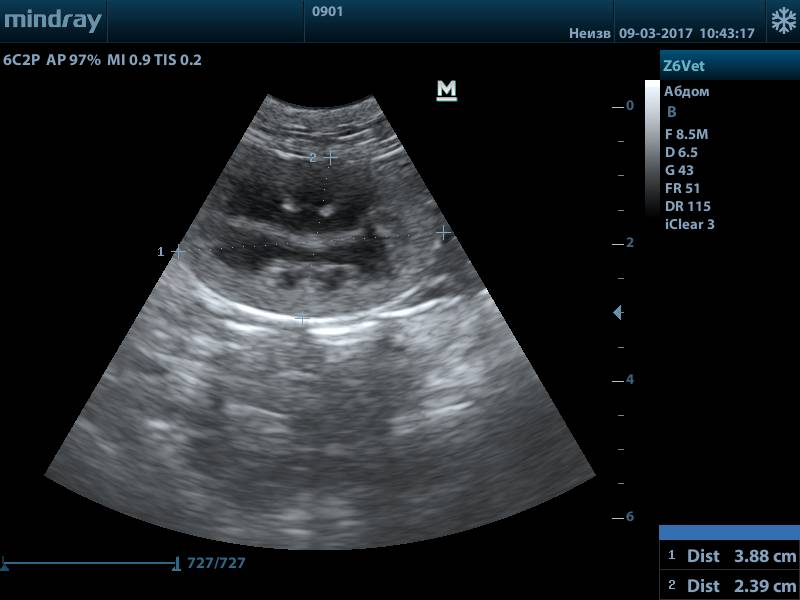

Оценка паренхимы при подозрении на нефропатию

Пациент: Филя, кот, 9 лет

Жалобы: Увеличение потребления воды (полидипсия), частое мочеиспускание. Владельцы отметили, что стал менее активным.

Диагноз: УЗИ почек выявило умеренное снижение эхогенности паренхимы и нечёткость кортико-медуллярной дифференцировки — признаки начальных изменений при хронической болезни почек (стадия IRIS 2).

Что дало УЗИ: УЗИ позволило оценить структуру тканей почек и подтвердить наличие функциональных изменений до выраженной азотемии. Это дало возможность начать раннюю коррекцию до прогрессирования болезни.

Результат: Назначена низкобелковая диета, нефропротекторы и контроль гидратации. Через 3 месяца — стабильные лабораторные показатели, улучшение активности.